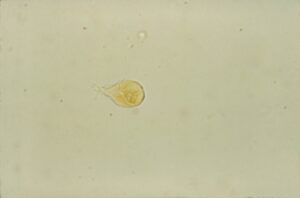

寄生虫やウイルスの感染によって下痢の症状がみられます。例えば、コクシジウム症や回虫症、パルボウイルス感染症などが消化管に影響を与え、激しい下痢を引き起こすことがあります。

犬や猫の下痢の原因は寄生虫?顕微鏡でしか見えない寄生虫である原虫をご紹介します!